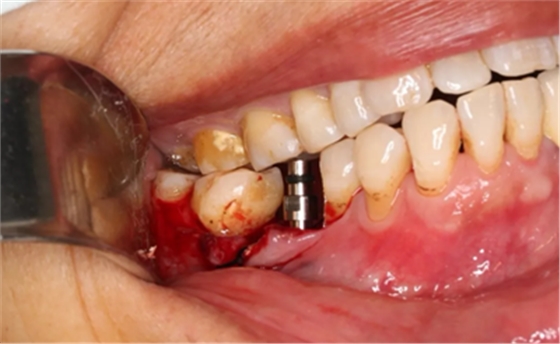

植入国产威高(WEGO)5.0×11mm种植体,检查种植体位于理想轴位。

(摄于2017年4月14日)

取下携带体,旋入封闭螺丝,潜入式愈合。